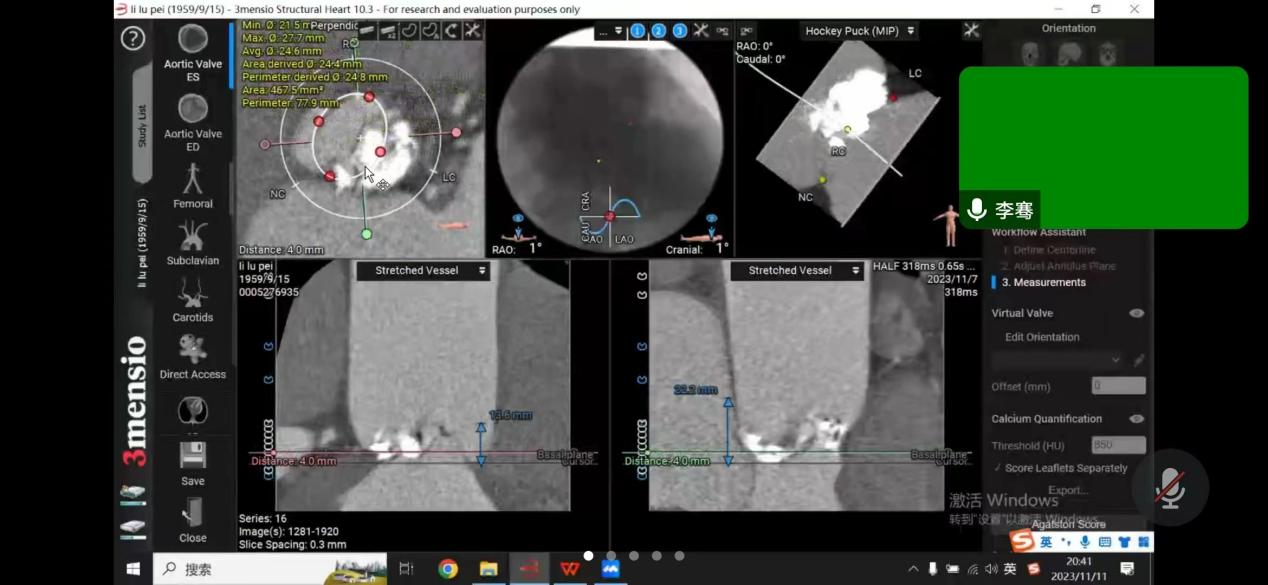

患者是一位64岁男性,反复胸闷憋气多年,未规律就诊,此次因慢性心力衰竭急性加重,心源性休克,多器官衰竭,由基层医院转至亚洲色吧 附二院。经过医院ICU团队抢救治疗后,患者病情转危为安;随后为患者完善超声心动图检查,提示主动脉瓣病变,TYPE-0型二叶式主动脉瓣,主动脉瓣钙化、重度狭窄并轻度反流,二尖瓣中度反流,三尖瓣中度反流,主动脉瓣前向血流速度4.9m/s,峰值压差95mmHg,行主动脉瓣换瓣治疗指针。由于能够反应患者左心室收缩功能的射血分数(EF值)仅占23%,心功能差,基础情况差,升主动脉瘤样扩张,收缩期心室增大明显,左室内径达60mm,心尖薄,不能承受开胸换瓣手术。心内科介入下行TAVR治疗的难度在于该病人为一例典型Type0型二叶式主动脉瓣重度狭窄患者,人工瓣膜定位及锚定难度大,患者瓣叶重度钙化,存在人工瓣膜形变、瓣环撕裂、根部损伤以及术后出现瓣周漏等风险。楚天舒主任团队对患者病情进行整体评估后,将患者情况汇报医院医务处,医务处组织心血管内科、麻醉手术科、心脏血管外科、重症医学科等进行术前多学科联合会诊,结合患者实际情况,多次讨论,为患者制定最佳手术方案,最后决定给该患者行介入导管微创瓣膜手术(TAVR)。多位专家一起制定了详尽的诊疗及手术方案,并准备了多套的应急预案。

11月12日下午,楚天舒主任团队成功为患者进行了TAVR换瓣治疗,手术中通过导管测量得到植入前心室主动脉压力差大于90mmHg,提示主动脉瓣狭窄已严重阻碍心脏正常泵血工作。人工瓣膜成功植入后,可见人工瓣膜瓣叶开阖自如,心脏对外泵血压力明显减轻,导管测得压力阶差降至10mmHg以下,血流动力学即刻得到改善。这提示着患者的主动脉瓣狭窄情况,已较前大为缓解,手术圆满成功。术后患者生命体征平稳,带气管插管安全返回ICU特护。一天后,患者被转回心血管内科二病区继续治疗。在心血管内科二病区全体医务人员的精心治疗与护理下,患者于17日顺利出院。